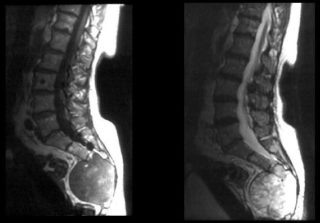

Остеохондрома в крестцовом отделе позвоночника

Остеохондрома

Остеохондрома – доброкачественное образование, которое формируется вместе с развитием скелета. Поражает детей и молодых людей в возрасте от 10 до 25 лет. Размер остеохондромы достигает 12 см. Не доставляет никаких неудобств, пока имеет небольшие размеры. По мере роста воздействует на сосуды и нервные окончания. При пальпации обнаруживается плотное, безболезненное образование. Кожные покровы в этом месте не гиперемированы, местная температура держится в норме.

Остеохондрома – это доброкачественная шишка на спине на позвоночнике, образовавшаяся из костной ткани. Диагностируется в возрасте 10-ти – 25-ти лет.

Симптомы обычно отсутствуют. Можно случайно прощупать шишку на спине. Если она сильно разрастается, то сдавливает нервы, мышечную ткань. Вследствие этого наблюдаются различные проблемы с двигательной активностью, чувственностью и пр. Имеют место переломы, инфаркты, тромбозы. Шишка на спине не болит.

Лечат остеохордому ортопеды – хирургически. Показан радикальный метод тогда, когда опухоль существенно деформирует скелет и имеет большой размер.

Наркоз предварительно делается общий. После специалист удаляет образование и основание ножки. От костной пластики можно воздержаться.